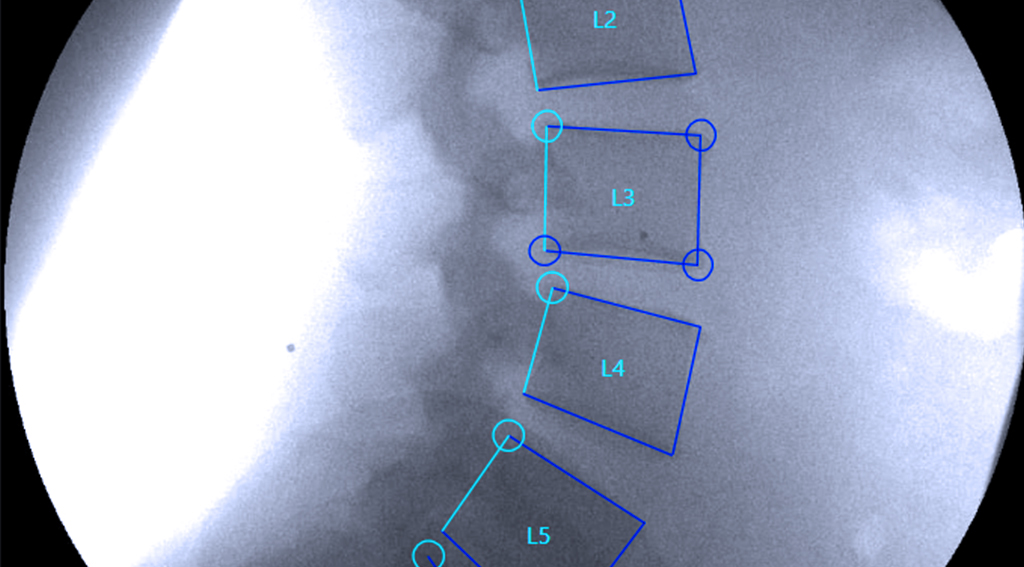

Motion matters because most spine injuries reveal themselves only when the vertebrae move. Static images hide the instability that causes recurring pain, slow recovery and missed diagnoses. A motion study shows how each segment behaves under real forces, giving you a clearer picture of the true problem and a faster path to the right treatment.

Its technology provides precise motion data in millimeters and degrees, not subjective interpretations.

VMA gives you a clearer path to answers.

It identifies hidden ligament injuries, connects symptoms to real findings, and supports better decisions for care or case strategy.